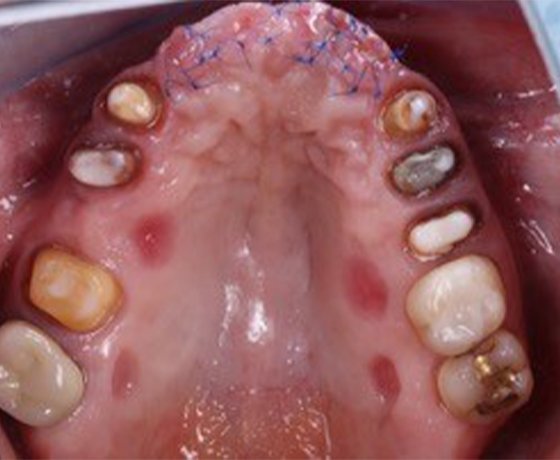

Occlusal view of a patient’s maxilla following an augmentation procedure in the anterior region and preparation of the canines and most of the posterior teeth.

All clinical images courtesy of Prof. D. Edelhoff